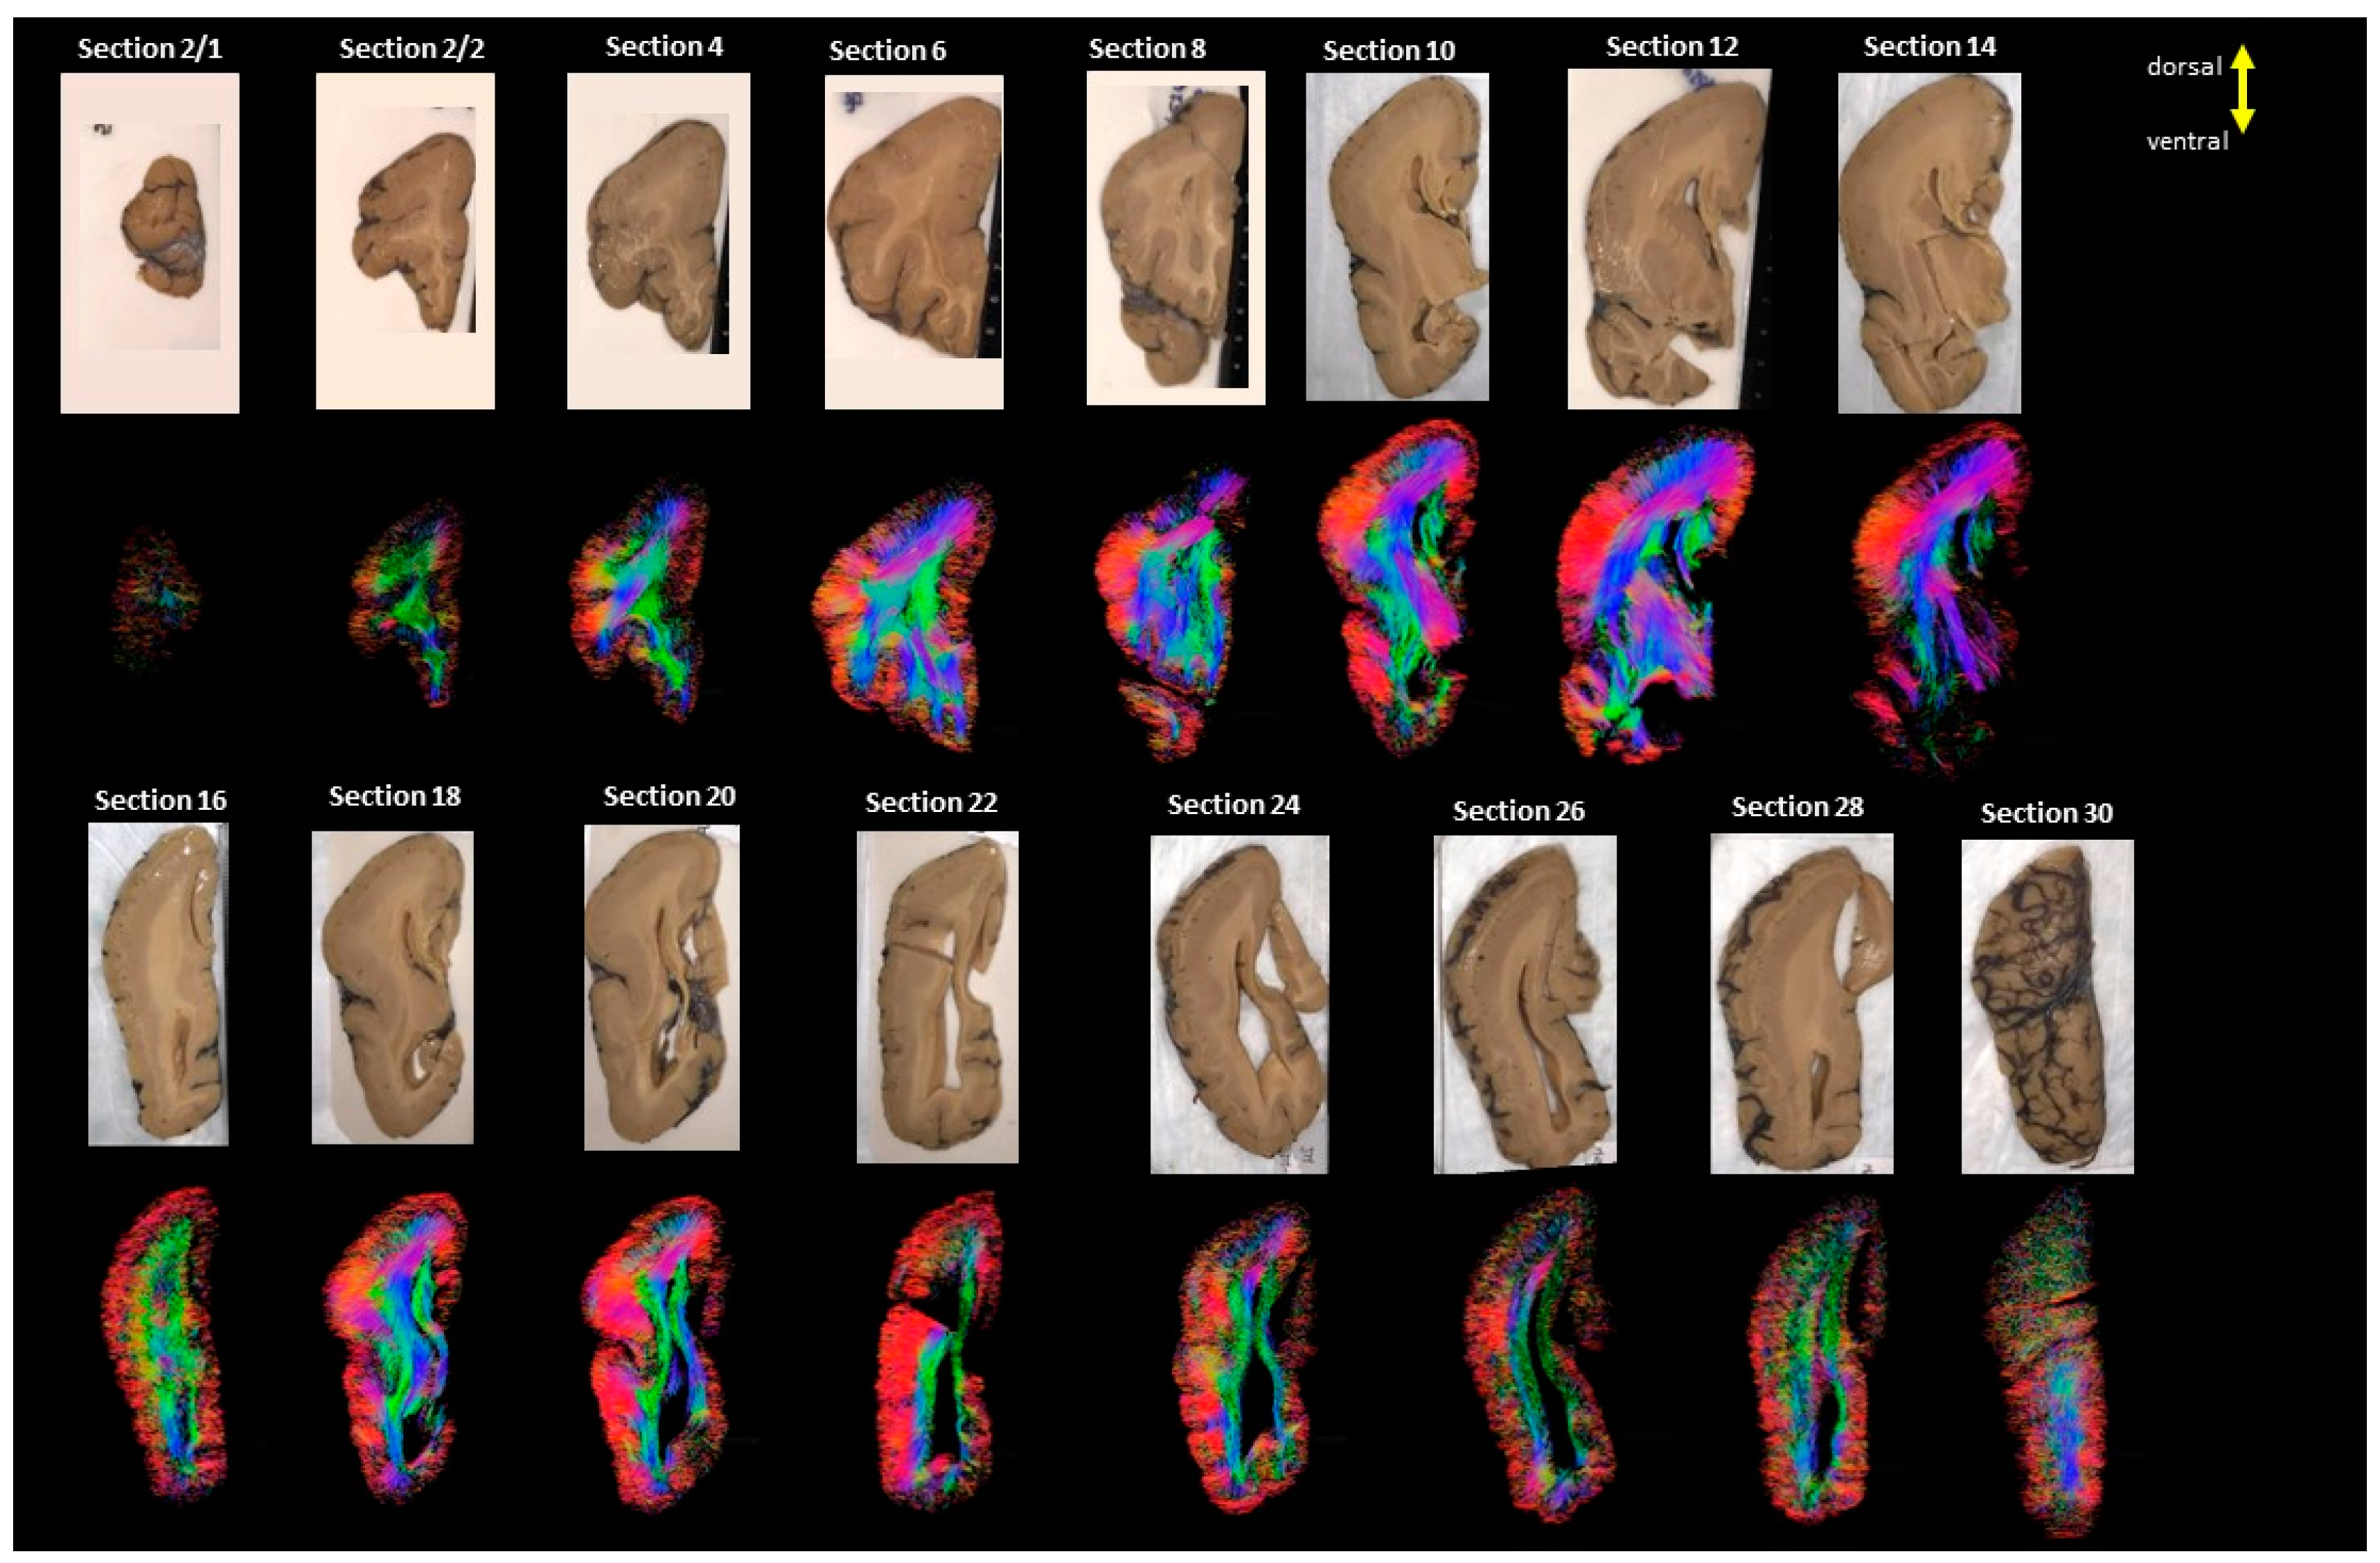

2. Materials and Methods

2.1. Diffusion MRI Acquisition and Analysis

2.2.2. Control

3. Results